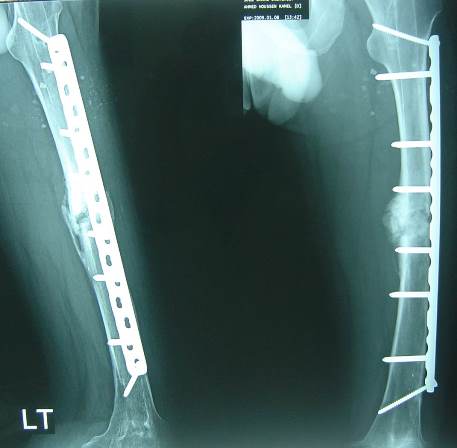

19-year-old male had fracture of femur which was treated by open IM nailing with aseptic non-union for 2 years where stiff knee arthroscopy and knee manipulation were done.

A few months later the patient presented with 2 nail breaks.

4 months later